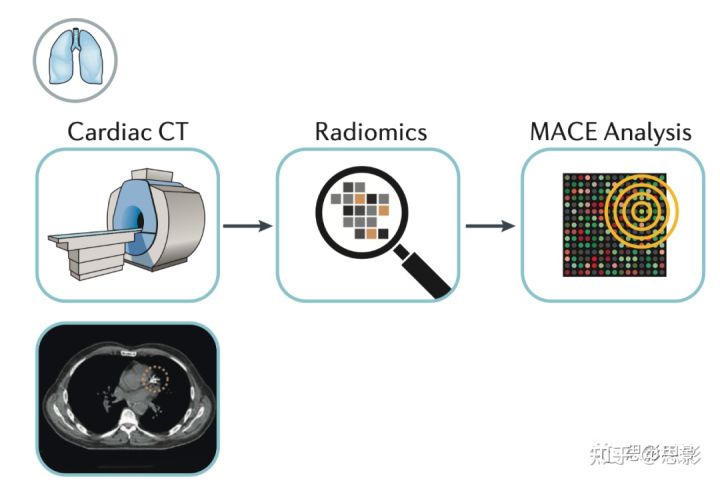

图2,心脏的影像组学

目前,量化CT上可见冠状动脉钙化的金标准是“阿加斯顿”法(基于强度和体积)。放射学特征可以改善量化,区分钙化和非钙化斑块,从而预测主要不良心脏事件(MACE)。